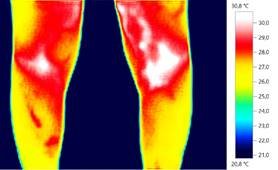

Phénomène de Raynaud Varices

et inflammation rotulienne